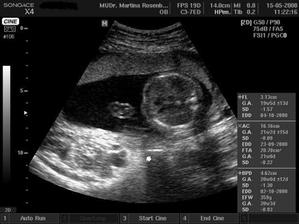

15.5. na kontrole vše v pořádku a asi opravdu budeme holčička, váhu máme 360 g a měříme 16 cm od temene hlavičky po prdelku. Příští kontrola 12.6. a o týden později 3D ultrazvuk...............